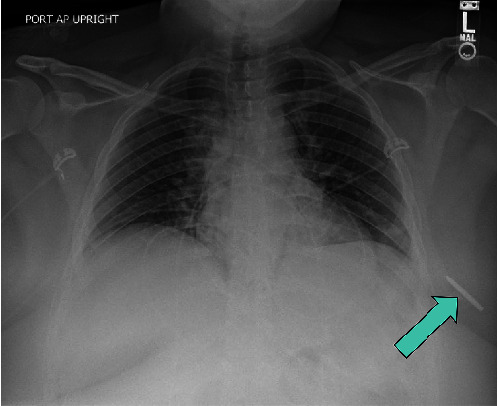

Background: Unintentionally retained foreign bodies in the breast are a rare phenomenon. Most reported cases are iatrogenically derived from surgeries and procedures. Only a handful of reported cases refer to noniatrogenic causes, including bullets, a sewing needle, and a headscarf pin. However, there are no reports to date that describe a retained foreign body in the breast after a motor vehicle collision or a similar traumatic event or from a decorative steering wheel emblem decal. Case Description: We report the case of a 25-year-old female who was involved in a motor vehicle collision with airbag deployment that led to a left breast retained foreign body, a steering wheel emblem decal. On presentation to the emergency room, she reported left chest pain associated with a puncture wound lateral to the left nipple. Imaging at that time was consistent with a metallic object embedded in the subcutaneous tissue of the left breast. Four months after the accident, the patient continued having daily burning pain in the associated area. As such, surgical excision was recommended, and wire-localized excision of the foreign body was subsequently performed. Grossly, the foreign body appeared as a metallic object with rhinestones, which the patient confirmed was a decorative emblem decal that was on her steering wheel. The postoperative course was uncomplicated, and follow-up examinations revealed resolution of the left breast pain. Conclusions: This case underscores a unique presentation after a common accident-a retained foreign body in the breast after a motor vehicle collision-and its successful surgical intervention leading to a favorable postoperative course. Notably, the National Highway Traffic Safety Administration recently advised drivers against adding decorative emblem decals to their steering wheels for this reason. The case therefore highlights safety precautions that should be taken regarding the addition of this type of accessory.

Abstract Image